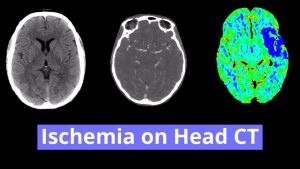

- Areas of hypoattenuation in the right middle cerebellar peduncle and superior cerebellum with loss of gray-white differentiation

- Patchy hypoattenuation in the left posterior periventricular white matter

Areas of hypoattenuation in the right middle cerebellar peduncle and superior cerebellum with loss of gray-white differentiation are concerning for acute/subacute ischemia in the right superior cerebellar artery distribution. Associated edema with resultant partial effacement of the right ambient cistern. No evidence of hemorrhagic transformation, herniation, or hydrocephalus. Recommend brain MRI for further evaluation.

Patchy hypoattenuation in the left posterior periventricular white matter represents age-indeterminate ischemia.